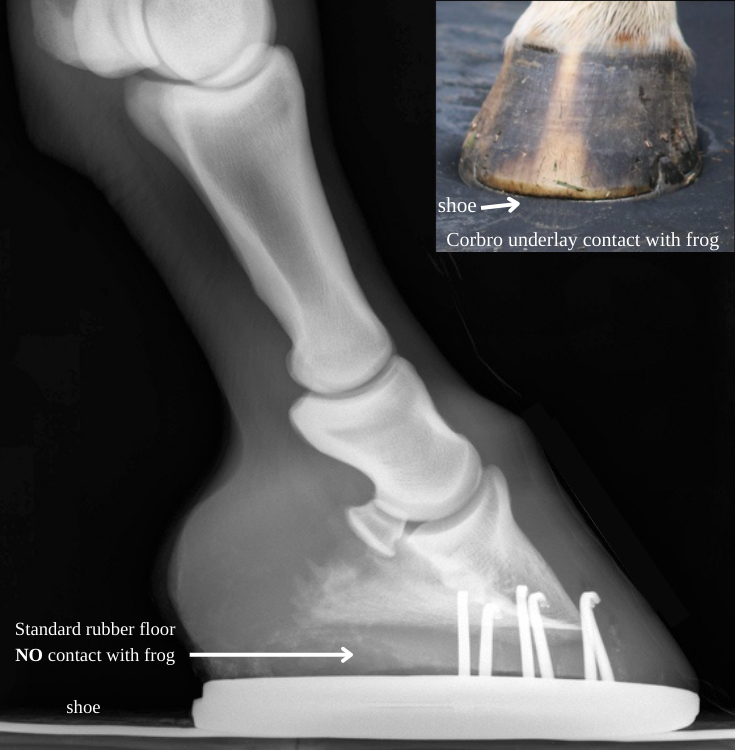

Horse Transport & The Frog

When a horse bears weight, the frog compresses to pump blood up the leg, ensuring proper circulation. Standard rubber flooring disrupts this process, causing poor circulation, discomfort, reduced performance, and potential issues like edema, cellulitis, and chronic progressive lymphedema(CPL).HM1 underlay stops these problems by supporting natural hoof/frog function and restoring proper circulation.